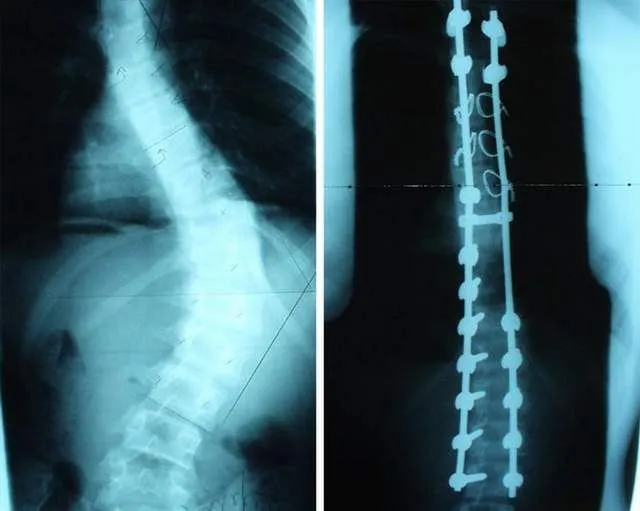

#5

ภาพเอ็กซ์เรย์กระดูกสันหลังก่อนและหลังได้รับการผ่าตัด